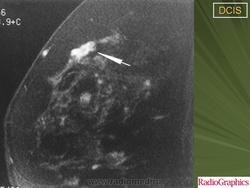

Обычно, ПКИС никак не проявляется и не выявляется при физикальном исследовании. Однако у небольшого числа женщин может отмечаться опухолевидное образование либо какие-то выделения из соска. Чаще всего протоковая карцинома выявляется на маммографии. Дело в том, что «старые» раковые клетки отмирая, не успевают полностью утилизироваться. В результате этого эта область пропитывается солями кальция (так называемое обызвествление) – образуются микрокальцинаты. Эти микрокальцинаты как раз и выявляются на маммограмме. В случае если полученные результаты маммографии врач считает подозрительными на рак, проводится следующий этап диагностики – биопсия.

Часто на маммограммах в области опухоли выявляются микрокальцинаты, что связано с том, что в опухоли происходит омертвление ее клеток (некроз), которые в последствие пропитываются солями кальция. Опухоль при инвазивной карциноме может быть различных размеров, и у клеток может быть различное время деления, так что некоторые клетки растут быстрее других.